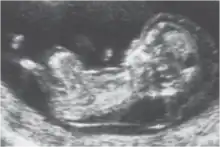

La clarté nucale, petite zone anéchogène (ne renvoyant pas d'écho en échographie) située sur le crâne d'un fœtus humain pendant le premier trimestre de grossesse, permet de dépister certaines anomalies congénitales, en particulier la trisomie 21.

La clarté nucale, comme son nom l’indique, se situe au niveau de la nuque du fœtus. Elle est due à un petit décollement entre la peau et le rachis et correspond à une zone dite anéchogène (c’est-à-dire qui ne renvoie pas d’écho lors de l’examen). Tous les fœtus présentent une clarté nucale au cours du premier trimestre, mais cette clarté disparaît ensuite.

La mesure de la clarté nucale[3] doit avoir lieu au cours de la première échographie de la grossesse, c’est-à-dire entre la 11e semaine et 13 semaine + 6 jours d’aménorrhée. Il est impératif que l’examen soit fait à cette période, car passé trois mois, la clarté nucale disparaît.